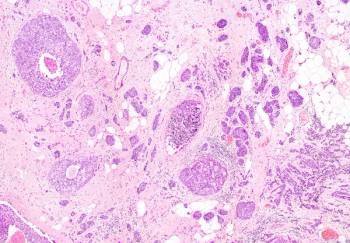

Although only a proportion of DCIS cases will progress into invasive cancer, the treatments available for DCIS are similar to treatments for invasive breast cancers.